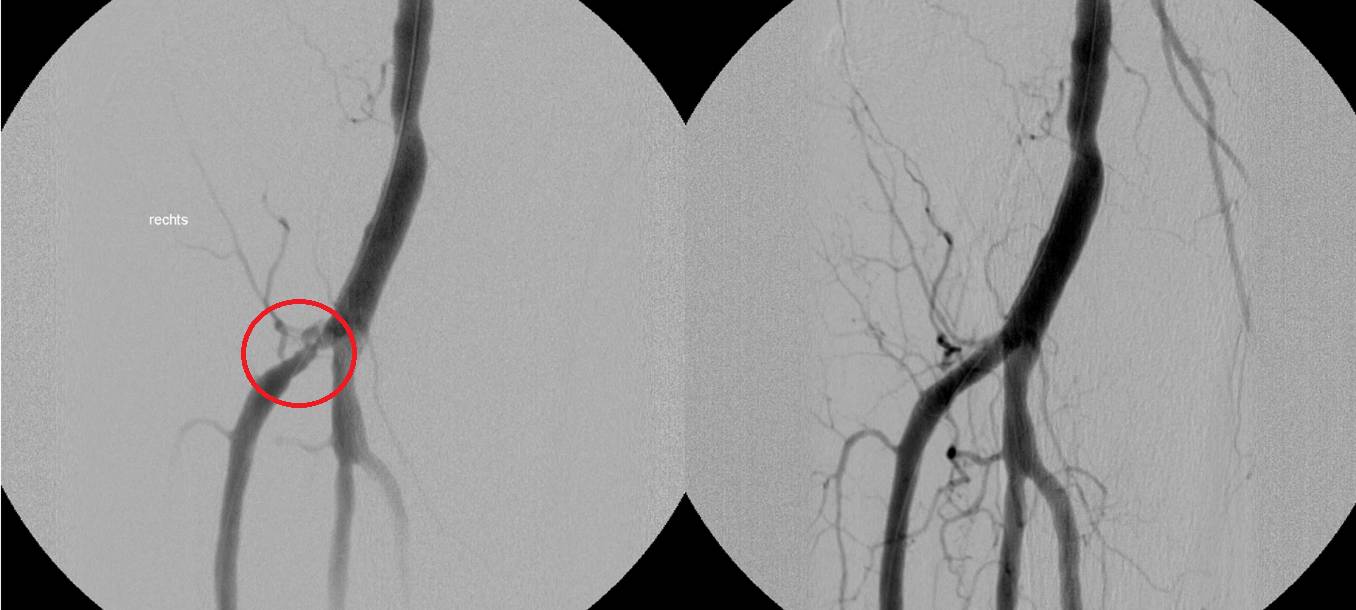

Unter der Leitung von Professor Dr. Giovanni Torsello, Chefarzt der Klinik für Gefäßchirurgie, behandelte das Team mit dem neuen Stent zwei Patienten mit einer schweren arteriellen Verschlusskrankheit. Die Röntgenbilder zeigen die 70-prozentige Verengung der Unterschenkelarterie eines Patienten vor der Operation (links) und die erfolgreiche Wiederherstellung der Durchgängigkeit (rechts) mittels des selbstauflösenden Stents.

Beide Patienten hatten eine stark ausgeprägte Arterienverengung, wodurch eine Amputation des Beines drohte. Die innovative Gefäßstütze wurde minimalinvasiv in die Unterschenkelarterie eingesetzt. Sie besteht aus einer Aminosäure, die Proteine bildet und die natürliche Funktion der Arterie wiederherstellen soll. Zudem ist ein Medikament enthalten, das eine erneute Gefäßverengung verhindern soll. Das Besondere an dem neuen Stent: Er ist bioresorbierbar, das heißt er zersetzt sich, nachdem der Blutfluss der Arterie sich regeneriert hat. "Das ist ein großer Vorteil gegenüber Metallstents oder Ballonkathetern, denn solche Fremdkörper, die dauerhaft verbleiben, können Langzeitrisiken mit sich bringen", erklärt Prof. Torsello.

Der Stent aus Polycarbonat ist die einzige sich auflösende Gefäßstütze, die für die Behandlung von Patienten mit peripherer Arterienerkrankung unterhalb des Knies zertifiziert ist. Er wurde bei Herzkrankheiten bereits erfolgreich eingesetzt. Im Vorfeld haben die Gefäßchirurgen im St. Franziskus-Hospital die Produktneuheit aus den USA in einer kontrollierten Laborumgebung umfangreich auf Praktikabilität untersucht. Im Gegensatz zu resorbierbaren Vorgängermodellen zeigt das neue Präparat deutlich weniger entzündliche Reaktionen während des Abbauvorgangs. "Es ist außerdem sehr gut im Röntgen sichtbar und kann deswegen exakt platziert werden", so Oberarzt Dr. Michel Bosiers, der die Eingriffe gemeinsam mit Prof. Torsello durchgeführt hat.